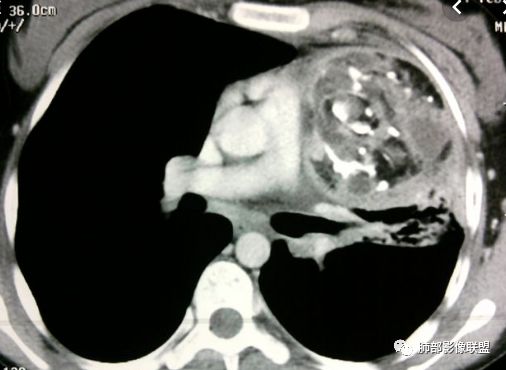

三个石头:前纵隔占位,不规则分叶肿块,内斑片状,点状钙化,内乳动脉增粗,肿块延迟强化。考虑良性占位,疾病谱畸胎瘤,胸腺瘤,巨淋。

弹指之间:定位:1.非肺内来源,2.纵隔或胸膜来源;内乳动脉增粗,cor示与胸膜关系密切;

定性:特点是粗大钙化,延迟强化;首先排除畸胎瘤(无脂肪、有延迟强化);胸腺肿瘤的粗大钙化罕见;综合:SFT>胸腺瘤(高危)。

滴水海:胸膜掀起定位纵隔,明显分叶,大块钙化,中度不均强化,从钙化特点入手,可见于畸胎瘤,巨淋,胸腺瘤,类癌,结核球,软骨瘤,可能性依次递减。巨淋强化不是太高,周围无增粗血管和淋巴结。如此明显分叶,若是胸腺瘤则是B3型及以上了,但其大块钙化似乎少见,明显坏死也没看到,对周围也未见明显侵犯。上二者少见表现或许有故次之。类癌若位于纵隔一般胸腺类癌,其钙化特点见得少,增粗迂曲血管多见,不典型,若是肺内类癌则可能性增大。结核球强化又太高。软骨瘤见的极少,曾见过一例心包软骨肉/瘤,罕见

右前纵隔不规则肿块,分叶状,内见斑块状钙化,肺组织受压内移,胸膜抛起,胸膜下纵隔脂肪间隙不清,增强后轻度强化,右侧内乳动脉无明显增粗,定位于纵隔内,定性:畸胎瘤与胸腺瘤鉴别,形态不规则,分叶,钙化明显,右侧内乳动脉不粗,畸胎瘤可能>胸腺瘤。